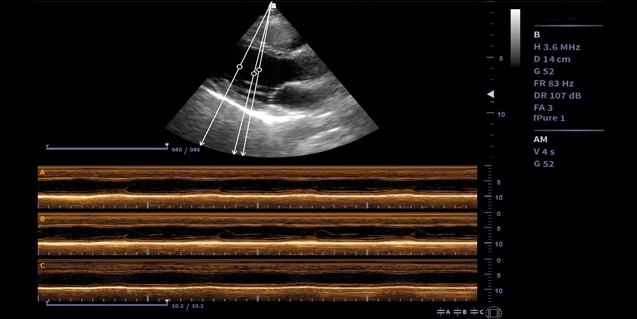

适用于成人心脏